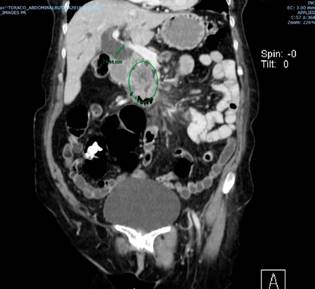

Se trata de una paciente de 72 años con cuadro clínico de obstrucción biliar secundaria a una masa en la cabeza del páncreas, cuyos estudios se describen a continuación: los niveles de bilirrubinas iniciales totales se encontraron en 12,32 mg/dL a expensas de la directa, que es de 10,8 mg/dL; tomografía de abdomen total que reportó neoplasia en la cabeza del páncreas, rodeando en 180° la vena mesentérica superior; confluente esplenoportal permeable; arteria hepática permeable; dilatación de la vía biliar intra- y extrahepática, y del conducto pancreático principal; aumento de la densidad de la grasa de la raíz del mesenterio con ganglios con ejes cortos (entre 5 mm y 6 mm) sospechosos por su realce; y lesión focal hepática en el segmento 6 de aspecto sospechoso para infiltración neoplásica, sin liquido libre (Figuras 1 y 2).